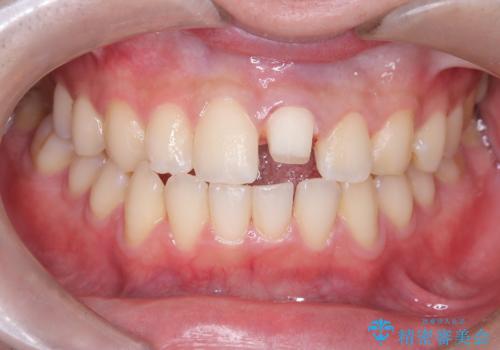

サーフィンで前歯をぶつけて歯が欠けた|かかりつけ医で治療困難と言われ当院へ来院|VPT(生活歯髄療法)で神経を保存|前歯の見た目も改善

- 歯冠破折により点状露髄を認めました。破折から1週間以内であったこと、また歯髄診断により生活反応が良好で保存可能と判断したため、VPT(生活歯髄療法)を行い神経の保存を試みました。